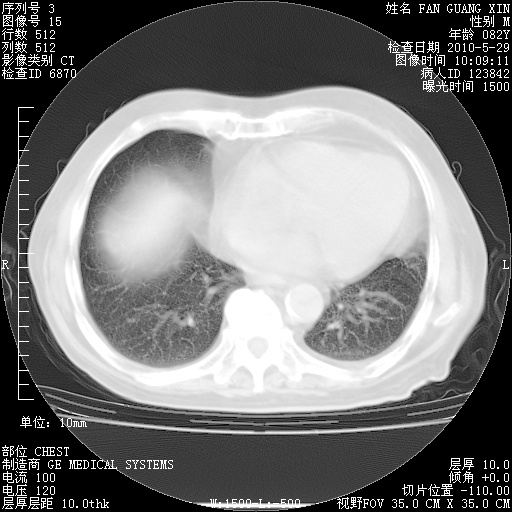

再治疗10天后的肺部CT

从白细胞总数和中性比例看好像合并感染。肺部纹理好像比上次多,支气管炎?其他感染?

阅读此次胸部CT,肺间质渗出性改变较入院时有吸收。目前从体温、白细胞、中性分叶明显增高,肯定存在细菌感染(发生医院感染哦,若无消化道及泌尿系统等感染的依据,肺部感染可能大)。若你院头孢哌酮舒巴坦钠耐药率较高,同意你的方案,若48小时体温仍高,可考虑使用碳青霉稀类抗菌药物,同时可予超声雾化、注意滴数时加大液体量。白蛋白33.30g/L较低哦,需加强营养等支持治疗。